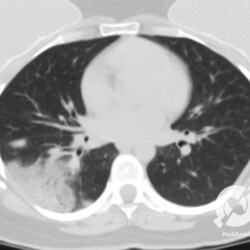

Os agentes etiológicos infecciosos são variados (bactérias, vírus, fungos, parasitas…), mas o que ocorre nos pulmões durante uma infecção por qualquer tipo de agente é a substituição do ar alveolar por secreção (pus, muco, eventualmente sangue ou necrose…) e com isso a manifestação radiográfica vai ser a mesma já que todas estas secreções apresentam a mesma densidade radiográfica: partes moles.

E o nome dado a esta alteração radiográfica que corresponde à substituição do ar alveolar por líquido é a consolidação alveolar.

Uma consolidação alveolar é, por definição, uma opacidade (imagem densa, branquinha) homogênea ou às vezes heterogênea (pela presença de calcificações ou cavidades), de limites mal definidos, exceto quando toca a pleura da parede ou das cissuras pulmonares. É um termo usado tanto em radiografia, como em tomografia computadorizada. Na tomografia, um outro termo é usado: vidro fosco, que é uma opacidade (branquinha mas não tanto como a consolidação), que borra o pulmão mas deixa ver os vasos de permeio (igual bigode de adolescente: dá pra ver todo o fundo).

Nós vamos mostrar aqui um pequeno apanhado de pneumonias de variados agentes, em diversos segmentos e lobos pulmonares, com extensões variadas. O objetivo é identificar o padrão radiológico de consolidação alveolar e não determinar o agente infeccioso, isso vai ser assunto para mais adiante. Aliás já antecipo que é fundamental saber localizar a lesão, porque alguns destes bichos gostam de determinados segmentos, alguns tumores também têm as suas preferências, então localização é fundamental. Se localização não fosse importante, um apartamento na beira do mar sairia o mesmo preço de um apartamento de frente pra BR-101, concordam?